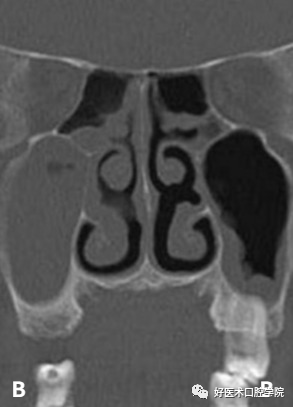

A:上颌窦粘液囊肿(周围可见骨质破坏) B:上颌窦积液(周围无骨质破坏)